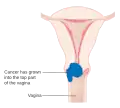

| Localização do cancro do colo do útero e exemplo de células normais e anormais | |

Cancro do colo do útero, cancro cervical (português europeu) ou câncer do colo de útero (português brasileiro) é o cancro que tem origem no colo do útero, ou cérvix.[1] Caracteriza-se pelo crescimento anormal de células que têm a capacidade de invadir ou de se espalhar para outras partes do corpo.[11] Na fase inicial geralmente não se observam sintomas. À medida que a doença avança podem-se manifestar sintomas como hemorragia vaginal, dores na pelve ou dores durante o ato sexual.[1] Embora a hemorragia após o ato sexual possa não ser grave, pode também ser um indicador da presença de cancro do colo do útero.[12]

Estadiamento

O câncer do colo do útero é estadiado a partir do sistema estabelecido pela Federação Internacional de Ginecologia e Obstetrícia (FIGO), que se baseia mais no exame clínico do que nos achados cirúrgicos. Apenas os testes a seguir podem ser usados no estadiamento da doença, quando se utiliza o sistema FIGO: palpação, inspeção, colposcopia, curetagem endocervical, histeroscopia, cistoscopia, proctoscopia, urografia intravenosa, conização e radiografia do tórax e do esqueleto.

Estádio 1A

Estádio 1A -

Estádio 1B

Estádio 1B -

Estádio 2A

Estádio 2A -

Estádio 2B

Estádio 2B -

Estádio 3B

Estádio 3B -

Estádio 4A

Estádio 4A -

Estádio 4B

Estádio 4B